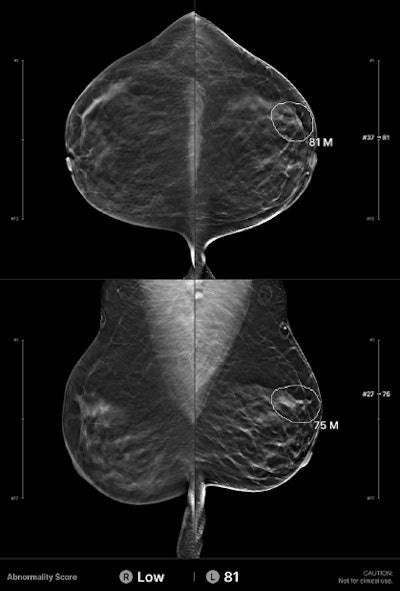

Example of an interval cancer retrospectively detected by an AI algorithm. A 41-year-old woman presented for a screening digital breast tomosynthesis (DBT) examination; its findings were interpreted as negative. Ten months later, the patient presented with a lump in the left breast and was subsequently diagnosed with grade 3 invasive ductal carcinoma. At retrospective evaluation of the initial screening mammogram, the AI algorithm marked a suspicious lesion (white outline) in the left breast, with high scores of 81 on the craniocaudal view and 75 on the mediolateral oblique view. This area of architectural distortion corresponds to the cancer that was subsequently diagnosed.Example of an interval cancer retrospectively detected by an AI algorithm. A 41-year-old woman presented for a screening digital breast tomosynthesis (DBT) examination; its findings were interpreted as negative. Ten months later, the patient presented with a lump in the left breast and was subsequently diagnosed with grade 3 invasive ductal carcinoma. At retrospective evaluation of the initial screening

mammogram, the AI algorithm marked a suspicious lesion (white outline) in the left breast, with high scores of 81 on the craniocaudal view and 75 on the mediolateral oblique view. This area of architectural distortion corresponds to the cancer that was subsequently diagnosed.